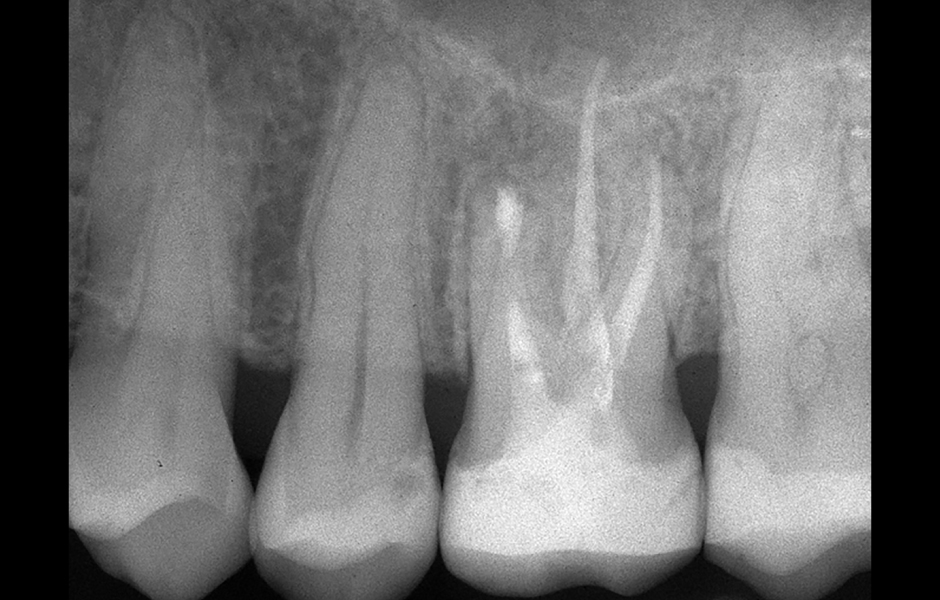

Obr. 4.1: Předoperační snímek horního levého prvního moláru. Oba kanálky mesiobukálního kořene byly kompletně kalcifikované a nebylo možné je ortográdně zprůchodnit.

Obr. 4.4: Pooperační rentgenový snímek zobrazující retrográdní výplň z bílého MTA.

Obr. 4.6: Kontrola po třech letech se zhojením léze.